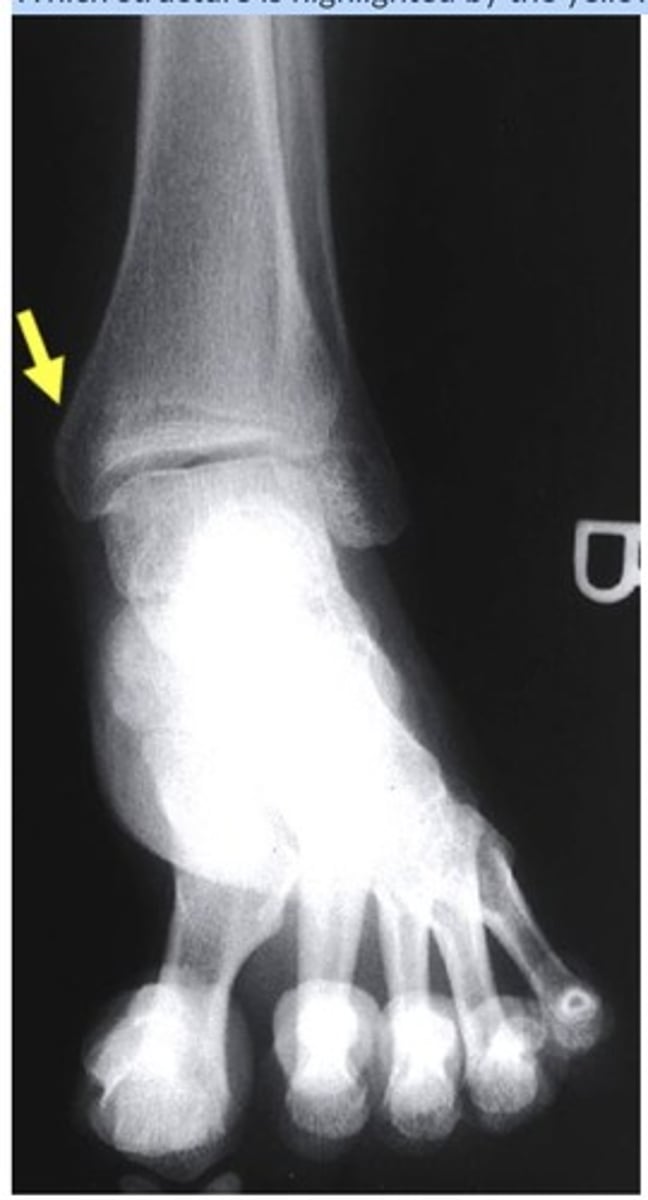

Which structure is highlighted by the yellow arrow?

medial malleolus